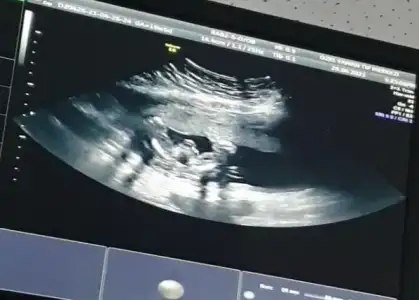

dr soylemeden siz gorun genital nub teorisi ( bebegin cinsiyeti)

Banada cinsiyet tahmini yapar mısınız

• IMG_20210430_093326.webp

IMG_20210430_093326.webp

28,9 KB · Görüntüleme: 77